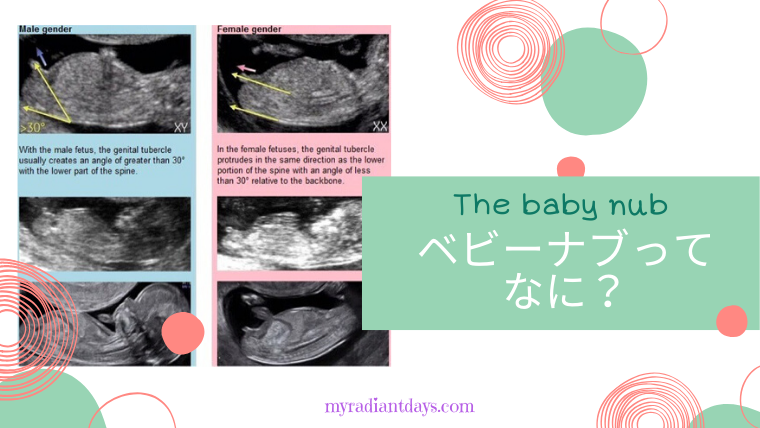

Babynub ベビーナブ 二人目に女の子を迎えたい

妊娠11 12 13週で性別が分かる Baby Nub ベビーナブ の見分け方を紹介

妊娠初期でも性別が分かる Baby Nub ベビーナブ ってなに 男児確定エコーあり わたしにとっては輝く日常